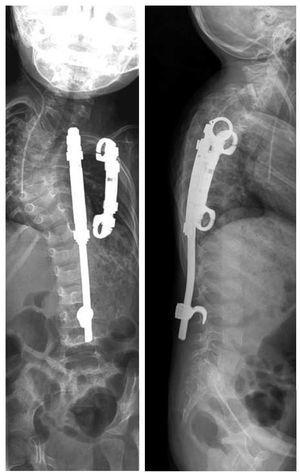

La indicación para la intervención fue en 16 casos una escoliosis congénita (figs. 24a-24c), en once casos una escoliosis neurológica y en doce casos una EIP. Las curvas se determinaron según Cobb. El ángulo de Cobb antes de la intervención medía un promedio de 65º (45-130º), y después de la intervención, un promedio de 32º (25-75º). En 18 pacientes tratamos una escoliosis torácica, en 18 pacientes una toracolumbar y en tres pacientes una lumbar (mielomeningocele). En 18 casos se utilizó un implante «costilla a costilla», en cinco casos un sistema de barra doble hasta la pelvis y en 18 casos un sistema híbrido (figs. 25 y 26).

Figuras 25a a 25c. a) Radiografía preoperatoria en proyección anteroposterior de una EIP con un ángulo de Cobb de 86º. b) Radiografía postoperatoria de una instrumentación «costilla a CL» realizada en una escoliosis toracolumbar progresiva. c) Radiografía postoperatoria en proyección anteroposterior después de 5 años. La curva se mantiene flexible y con buena corrección.

Figuras 26a y 26b. a) Radiografía postoperatoria en proyección anteroposterior después de corregir una escoliosis congénita mediante la técnica híbrida. b) Radiografía lateral postoperatoria.

Realizamos un total de 39 implantes primarios, 102 cirugías de expansión y 24 sustituciones de implante. Estas últimas fueron necesarias debido a la aparición de curvas compensatorias o porque los implantes se habían quedado pequeños como consecuencia del crecimiento. Cada niño fue intervenido entre una y nueve veces (figs. 25a a 25c).